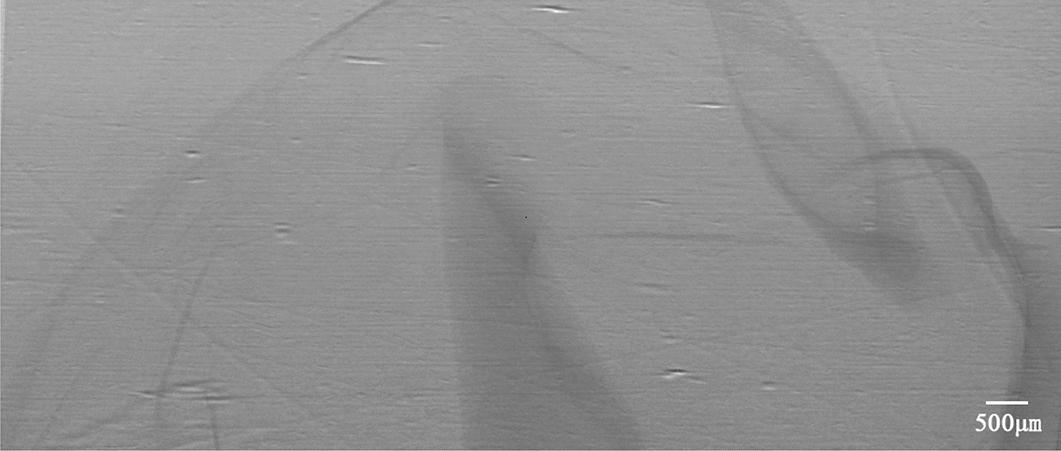

To intuitively understand the changes of gastric morphology and structure in different age groups, the XILPCI projection images of gastric specimens are shown in Fig. 1. Changes were observed at different week in rats. Figure 1A shows the ordered and regular tissues of a 4-week-old young gastric normal specimen, and the gastric walls are smooth without any hyperplasia. The XILPCI image are more detailed than the X-ray traditional image of a normal gastric specimen [5–8], as we could only see the overlapping walls of the stomach in the absorption images, and the images are very fuzzy with an unclear internal texture (as shown in Fig. 2).

Fig. 2.

An X-ray absorption image of a rat stomach